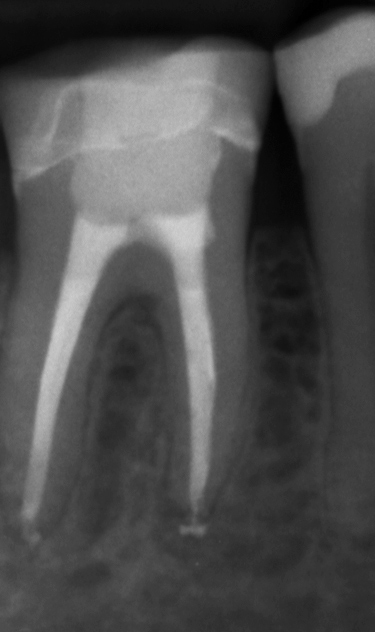

Eksempel på endodontisk behandling utført av tannlegestudent.

Endodontisk behandling ved utdanningsinstitusjoner har ofte god prognose [3][4][5], men behandling av molarer og revisjoner er teknisk krevende, og studenter rapporterer ofte usikkerhet ved slike prosedyrer [6][7]. Denne studien bekrefter at tannlegestudenter i økende grad utfører komplisert endodontisk behandling, noe som utfordrer undervisningen til å sikre nok mengdetrening på molarer og revisjoner for å opprettholde kvalitet og pasientsikkerhet.